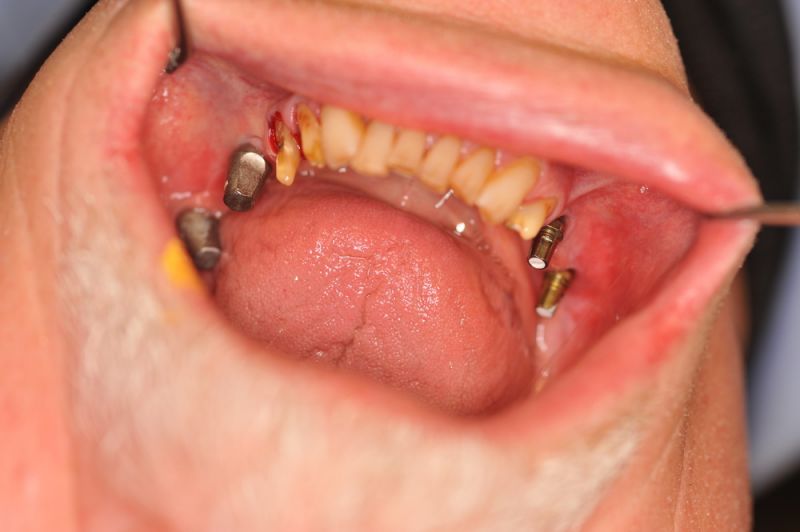

Beginn einer umfangreichen funktionstherapeutischen Rekonstruktion eines Patienten aus Ostholstein

Vor ca. 20 Jahren wurde der Patient umfassend funktionstherapeutisch versorgt. Bereits zum damaligen Zeitpunkt waren die Zähne des Patienten vorgeschädigt und es lag eine Parodontalerkrankung vor.

In der Zwischenzeit sind vorgeschädigte Zähne verloren gegangen und wurden zum Teil durch Implantate ersetzt.

Über eine mehrjährige Phase wurden immer wieder Laborgefertigte Dauerprovisorien eingegliedert, weil vor einer abschließenden funktionstherapeutioschen Behandlung erst noch andere Problemzonen beseitigt werden mussten.